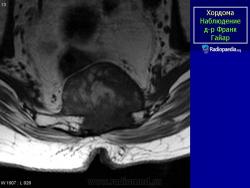

Хордома - медленно растущая злокачественная опухоль, встречающаяся в 1-4 % случаев злокачественных опухолей костей и образующаяся из остатков хорды (спинной струны). Локализация: хордома может развиваться в позвонках, большей частью шейных и грудных, но у половины больных - в крестцово-копчиковом отделе, а также в области турецкого седла, затылочной и верхнечелюстной областей. У мужчин хордома встречается в два раза чаще, чем у женщин. Основная часть больных - лица в возрасте 50- 70 лет. Хордома затылочной области редко превышает несколько сантиметров в диаметре, но при локализации в крестцово-копчиковой области она может стать гигантской (массой до 6,5 кг).

МР-изображения показывают большую гетерогенную твердую разрушающую массу, включающую большинство крестца и копчика, характерные для хордомы

Хордома крестца.